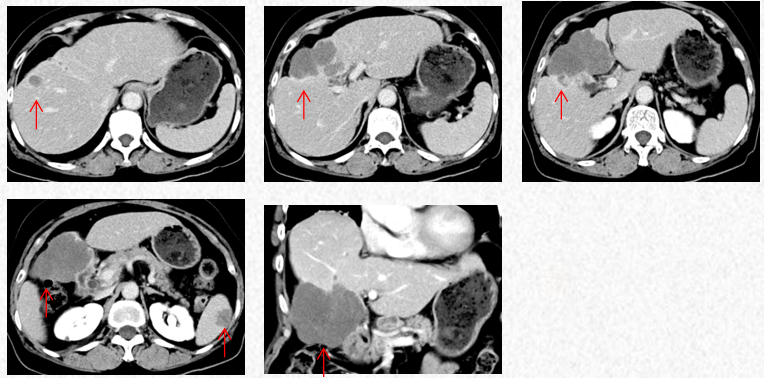

2022-11-30复查胸腹CT提示进展(PD)。

2022-11-30胸腹CT:肝肿物最大横截面积107*80mm(原病灶10*8cm),腹腔淋巴结最大10mm。新发脾脏转移瘤大小27*15mm。